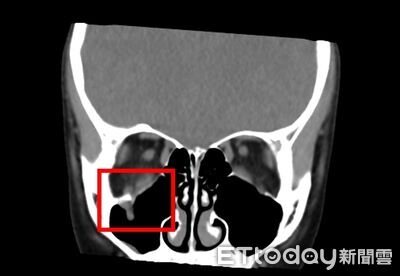

兒童和人發生碰撞,可能造成難以想像傷害。一名9歲女童在校園被同學的膝蓋撞到眼周,沒有造成明顯疼痛,也未留下瘀青,未料後來眼球卻無法轉動,送醫才發現眼窩竟已有「線性爆裂性骨折」,裂骨卡住眼眶內肌肉或軟組織;醫師說,這類傷勢應把握24至48小時治療黃金期,以免造成永久視覺障礙。 《詳全文...》